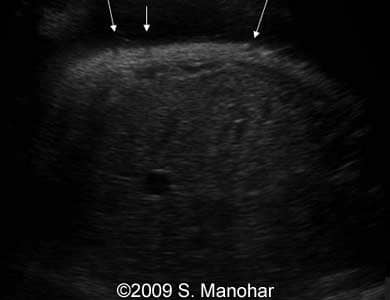

Images 1, 2: The images show an edema of the fetal eyelid"s ectropion (arrows).

1